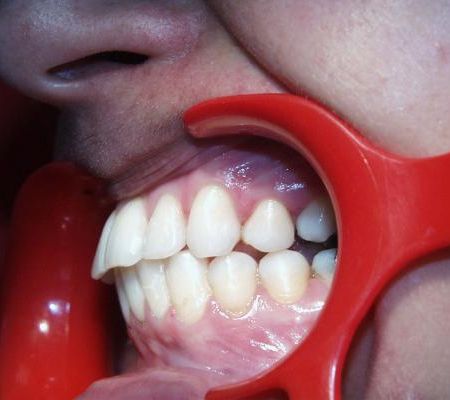

Im diesem Beispiel wird eine erwachsene Patientin vorgestellt, bei der nach kieferorthopädischer Vorbehandlung der Unterkiefer chirurgisch vorverlagert wurde. Eine Beseitigung der Stufe in Verbindung mit einer Entfernung zweier kleiner oberer Backenzähne ohne Chirurgie wie im Fallbeispiel 1 schied aus, weil diese Extraktionen im Rahmen einer früheren Behandlung, die andernorts durchgeführt worden war, schon vorgenommen waren.

Vor der Behandlung